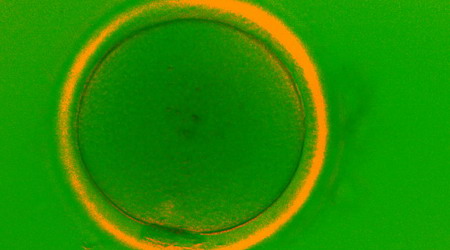

Самото делително вретено се образува в яйцеклетката и е свързано с формирането на ДНК на бъдещия нов човек. Неговият анализ е технология, която позволява да се направи оценка на характеристиките на женската репродуктивна клетка и да се определят нейните оплодителен и имплантационен потенциал. С напредъка на оптичните и компютърните технологии, делителното вретено на яйцеклетката се визуализира в реално време преди процеса на инжектиране със сперматозоид. В допълнение могат да се оценят нейните зрялост и качество.

Оценката на делителното вретено, разположението му в яйцеклетката, ако то е налично в нея, плътността на белтъци и други структури в обвивката й са изключително важни, тъй като именно те определят имплантационния потенциал на бъдещия ембрион. Анализът на делителното вретено на яйцеклетката и нейната обвивка (Spindle & ZP View) спомага за по-точно определяне на времето и начина на изпълнение на ICSI процедурата, така че да не се разстрои генетичният материал в делителното вретено, ако то е изместено.